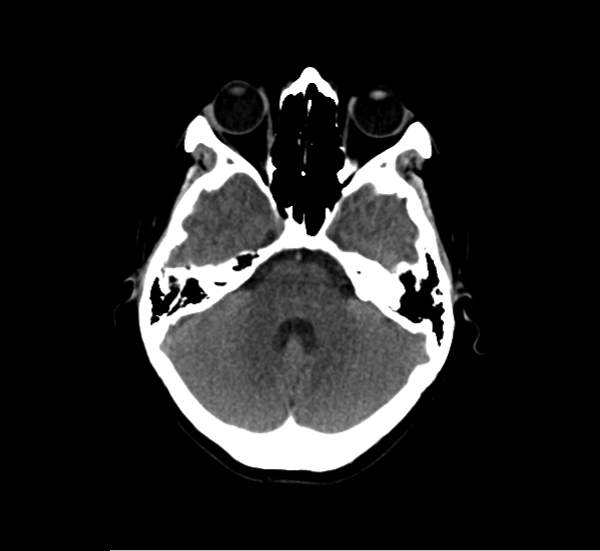

CT Brain Anatomy